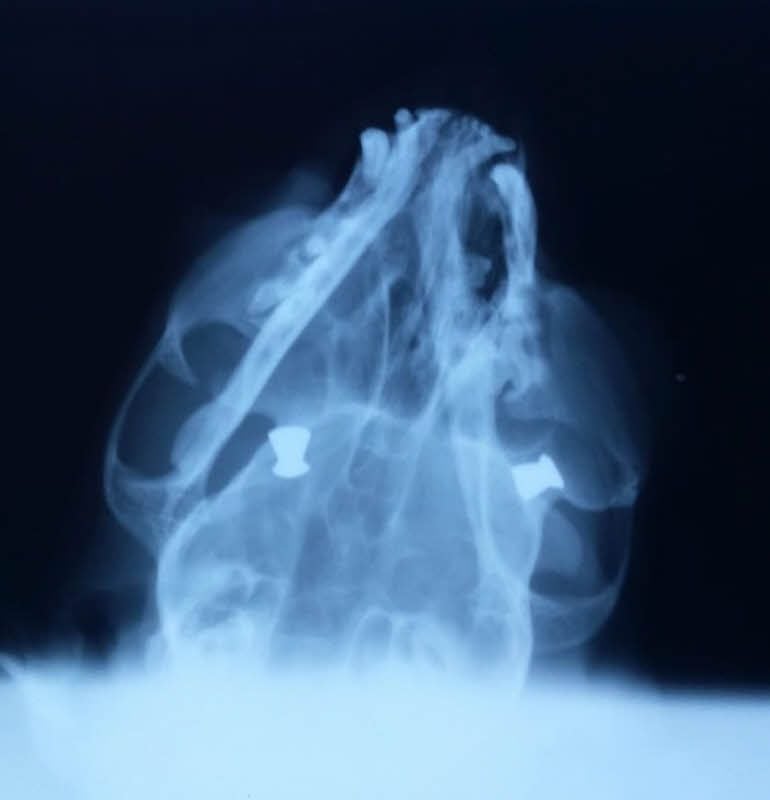

Am Montagvormittag entdeckte Christiane Ehrhardt den Kater schwer verletzt auf ihrer Couch. Sie rief ihre Schwiegertochter, die auch auf dem Grundstück lebt, und beide fuhren mit dem schwer verletzten Kater nach Naumburg zu einer Tierärztin. Diese vermutete erst, dass Sammy von einem Auto angefahren worden sei. Er blieb in der Praxis und wurde geröntgt. Da entdeckte die Ärztin auf den Bildern plötzlich zwei in den Augenknochen steckende Projektile eines Luftgewehrs.

Auf den Kater kann nicht einfach nur gezielt worden sein. „Er muss festgehalten und mit den Diabolos direkt aus nächster Nähe angeschossen worden sein“, vermutet Christiane Ehrhardt. „So etwas habe ich in meinen fast 40 Lebensjahren noch nicht erlebt“, ergänzt ihr Sohn.